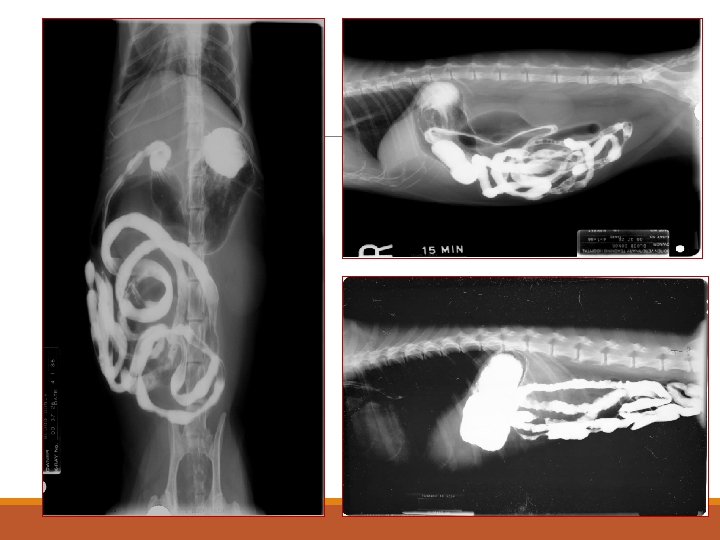

Contrast Studies of Intestine Indications ◦ Size, shape, mucosa of SI ◦ Suspect of SI disease ◦ Diagnosis of obstruction Contraindication ◦ Barium if suspected rupture of hollow viscous, use iodine (ionic) instead Procedure ◦ Preparation Interpretation ◦ Lumen diameter ◦ Mucosa

Intussuception